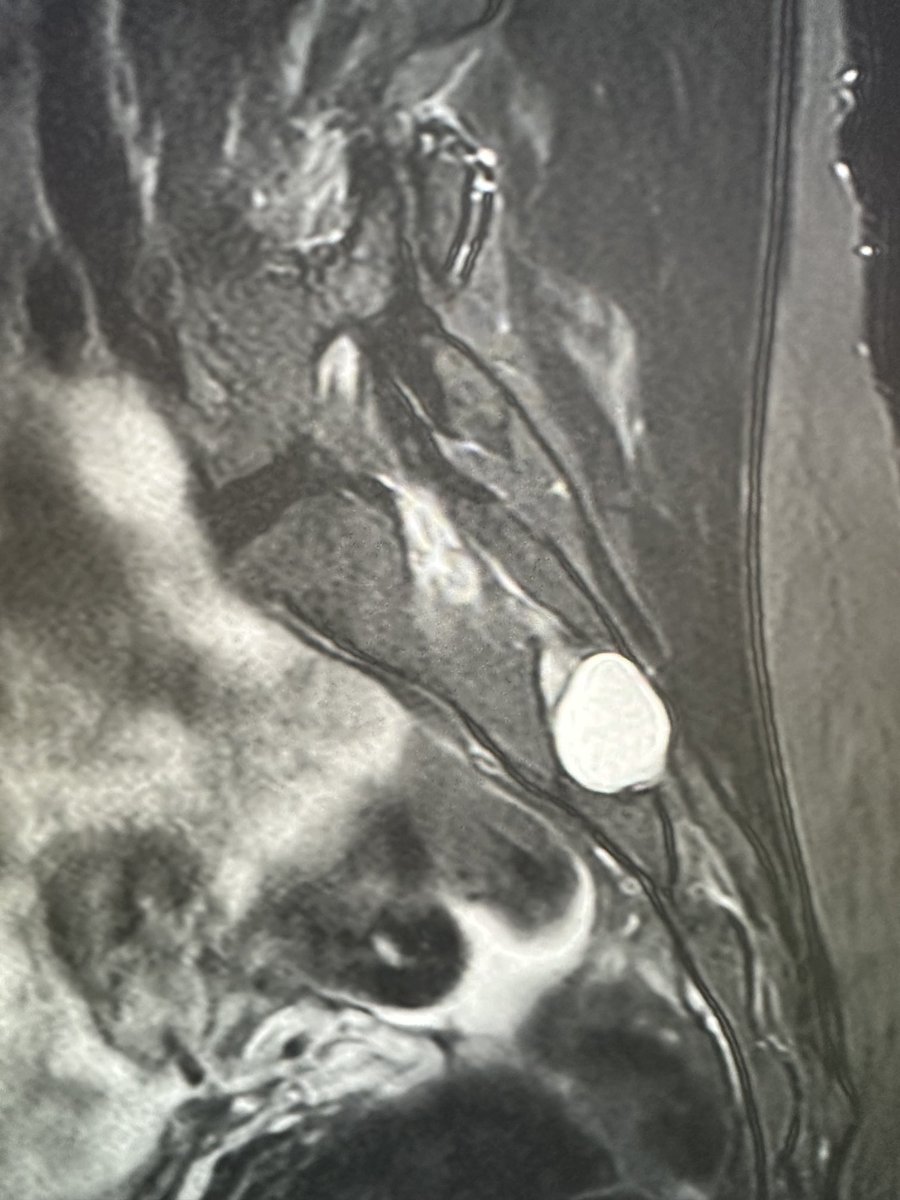

Young RHD pt in MVC with R shoulder dislocation and large cuff avulsion. Also w/ a DENSE brachial plexopathy with no motor or sensation below the deltoid. Axillary n. is ok. Everything distal to that is out. Plexus MRI shows edema w intact plexus Haven’t seen this in a bit